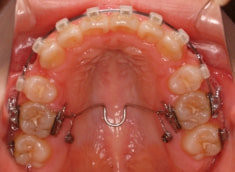

治療開始から5ヶ月後